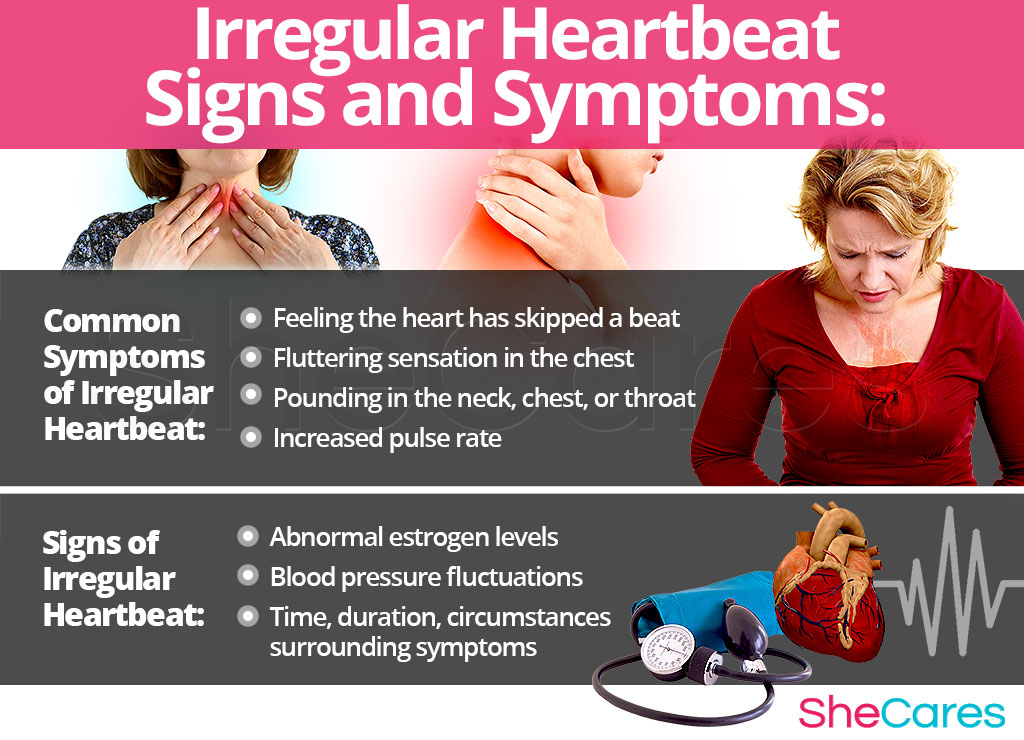

Erratic Heartbeat

Irregular Heartbeat Causes Protectzik

Can Too Much Calcium Cause Irregular Heartbeat